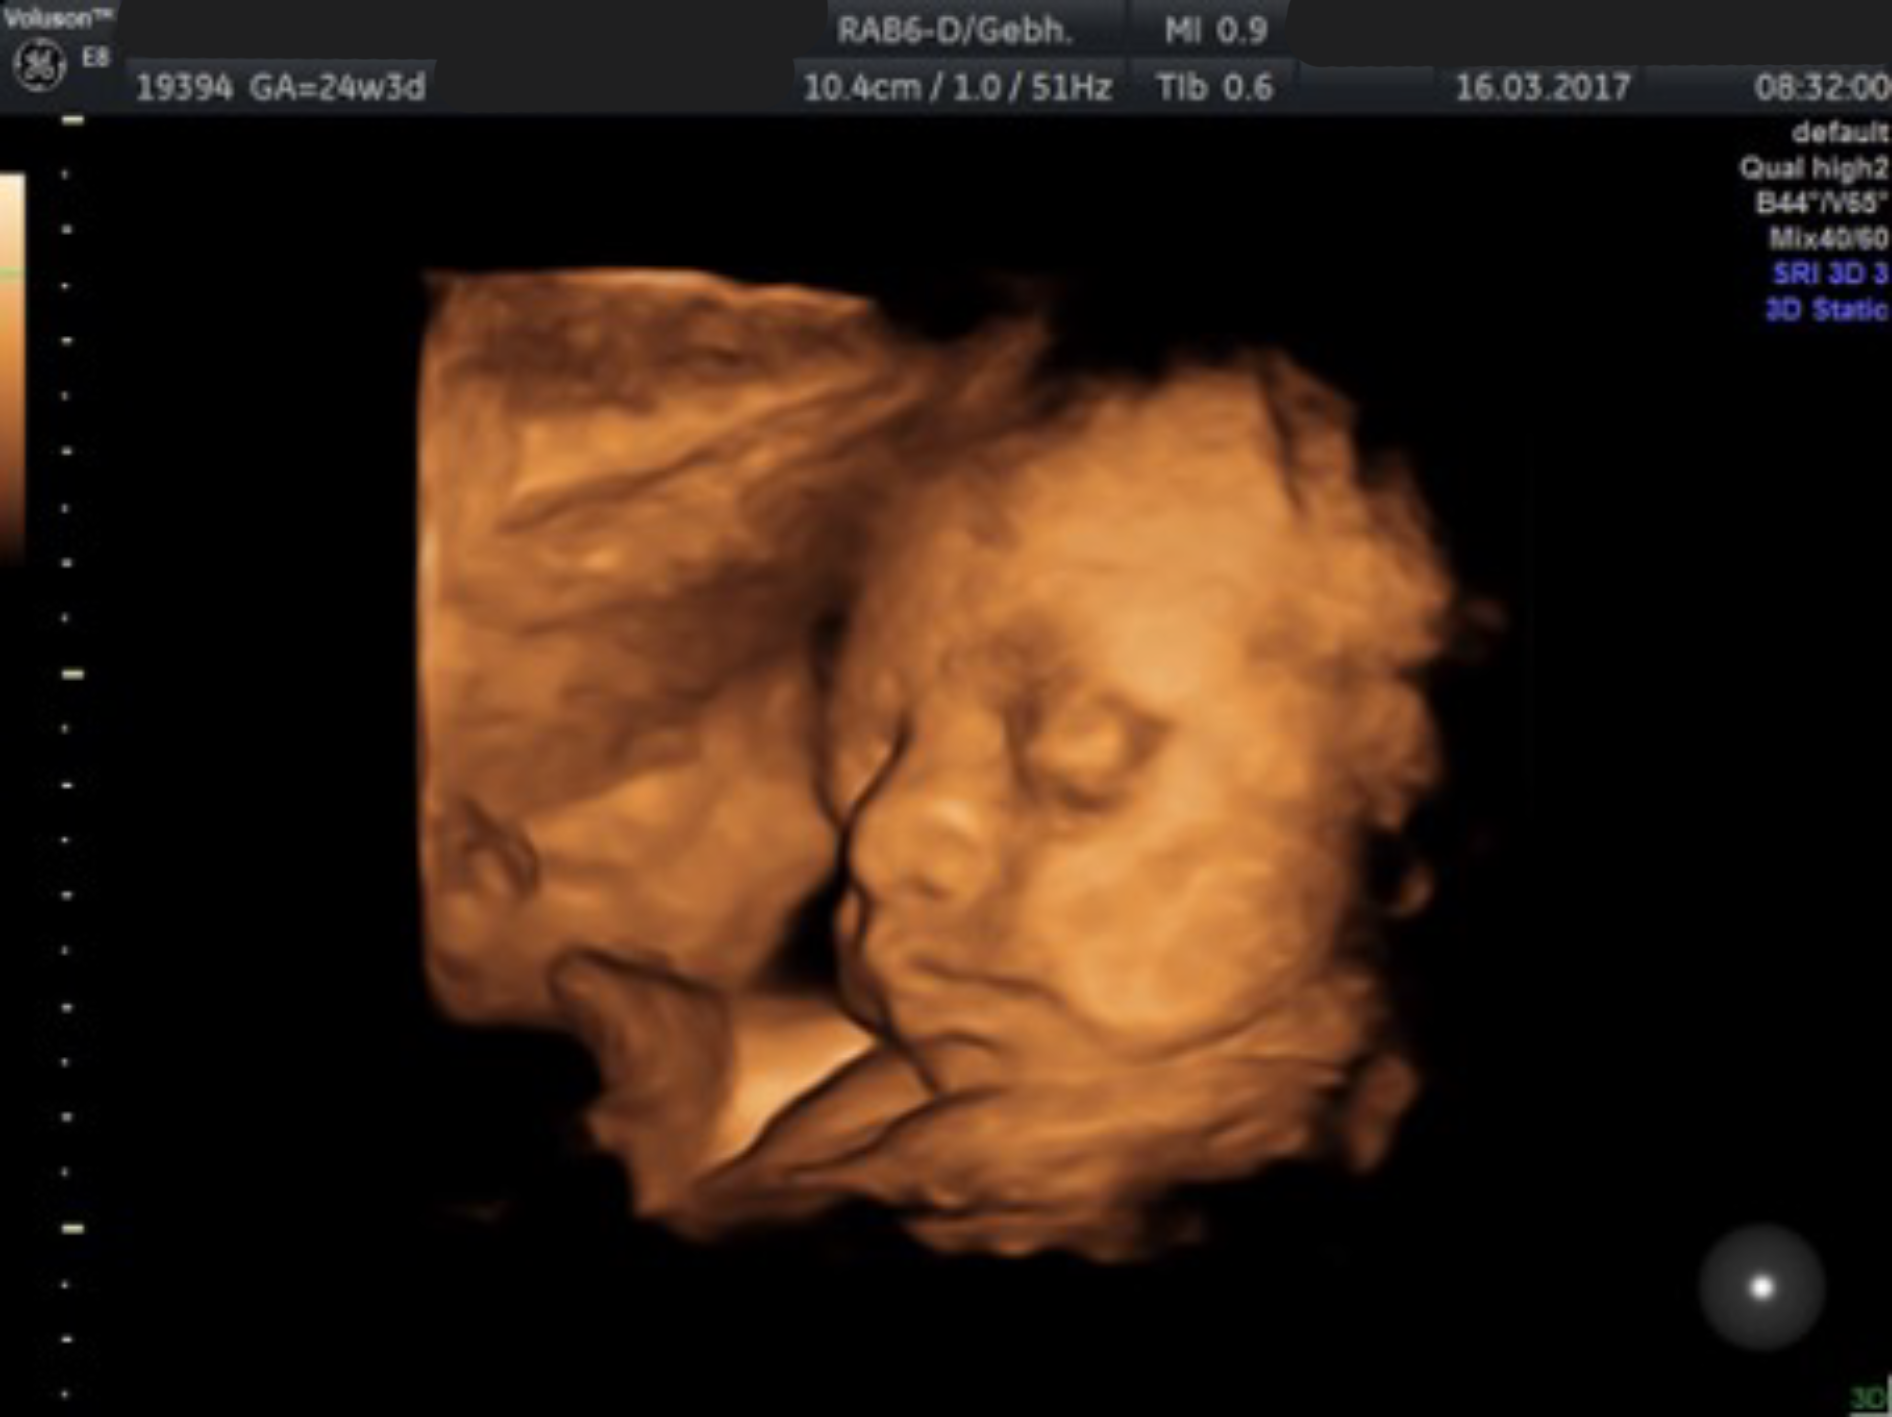

Ultraschall

Durch den Ultraschall kann die körperliche Entwicklung Ihres Kindes untersucht werden. Man kann verfolgen, ob das Kind gut wächst, ob sich die verschiedenen Organe zur richtigen Zeit am richtigen Ort und in richtiger Form entwickeln oder ob Hinweiszeichen für Störungen erkennbar sind.

Ultraschall in der 20. – 22. Schwangerschaftswoche mit Organfehlbildungsdiagnostik und Untersuchung der Blutversorgung nach den Richtlinien der DEGUM Stufe II

Mit einem hochauflösenden Ultraschallgerät werden dabei alle Organsysteme des Kindes gründlich untersucht um nach Hinweisen auf Fehlentwicklungen zu suchen. Besonderes Augenmerk liegt dabei auf dem Herzen, dessen richtiger Aufbau und Funktion mithilfe farbcodierter Blutflussmessungen (Doppleruntersuchung) überprüft wird.